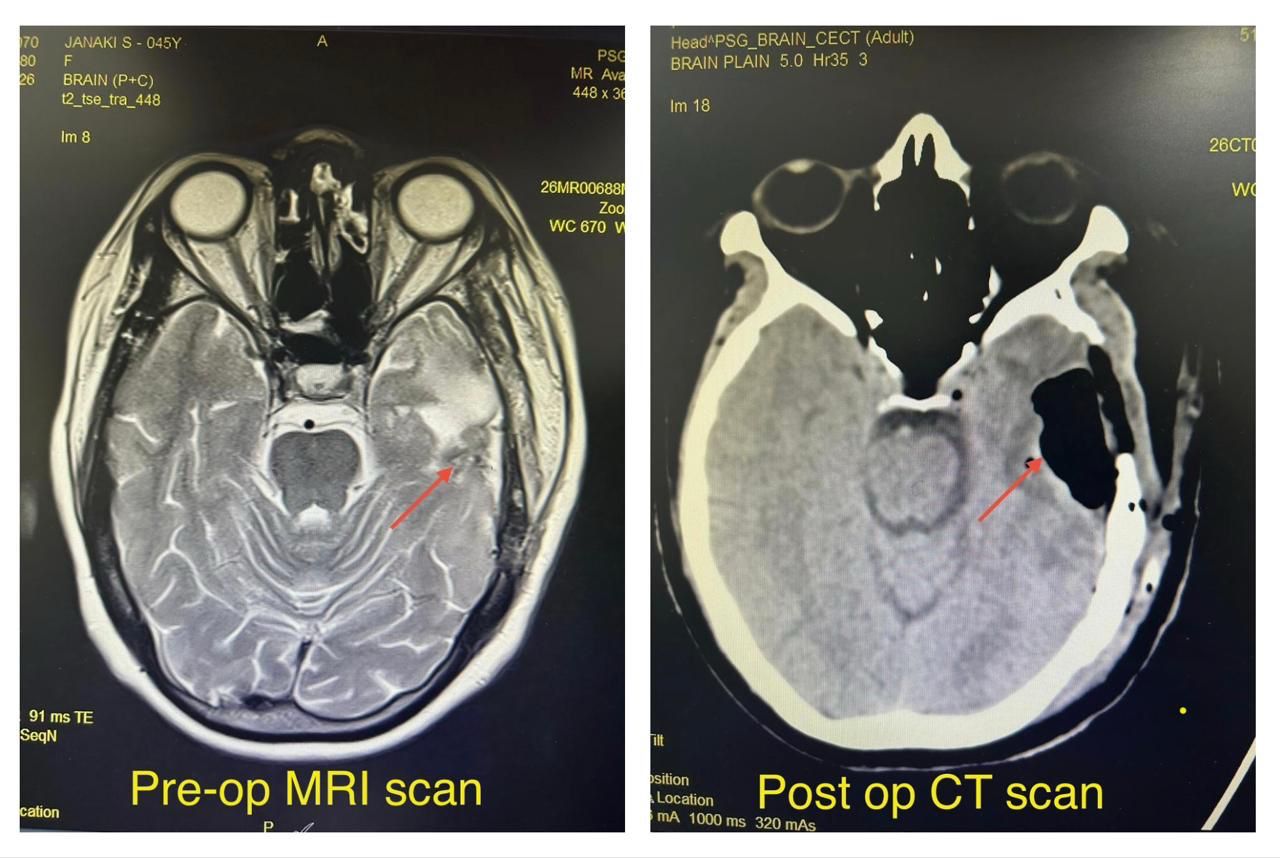

At PSG Hospitals, we continue to push the boundaries of advanced medical care with a strong focus on patient safety, precision, and quality of life. In a recent remarkable case, our Neurosurgery team successfully performed an awake craniotomy on a 45-year-old female patient who presented with persistent headache.

Detailed evaluation revealed a large insular tumor measuring 6.2 × 4 × 5.3 cm, involving the left temporal and parietal lobes. The tumor was located in the dominant hemisphere and affected critical regions responsible for speech and motor function (eloquent cortex). Despite the size and complexity of the tumor, the patient remained neurologically preserved, apart from her presenting complaint.

Given the tumor’s proximity to vital functional areas, the surgical team opted for an awake craniotomy—an advanced neurosurgical technique that allows real-time monitoring of brain function during the procedure. This approach is particularly crucial in cases where preserving speech, movement, and cognition is of utmost importance.

The surgery was completed successfully with total tumor removal, and importantly, the patient remained neurologically intact both during and after the procedure.